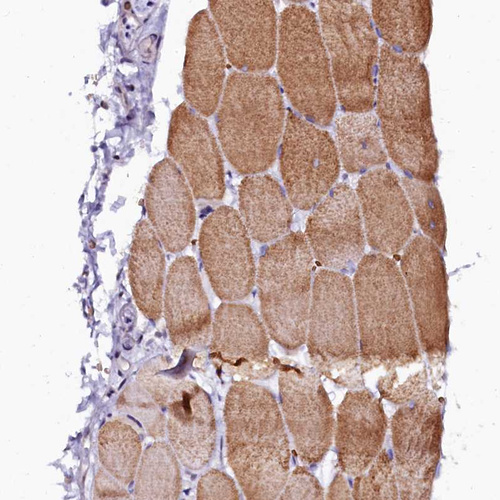

Immunohistochemical staining of human testis shows moderate nuclear/cytoplasmic positivity in Leydig cells.